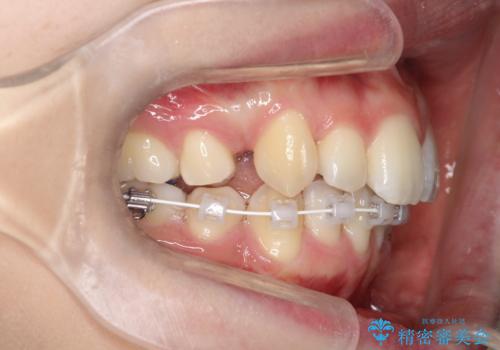

- ハーフリンガル

- 2年1ヶ月

目立たない装置をご希望でしたので、上下左右の歯を1本ずつ抜歯してハーフリンガルでの矯正を行いました。